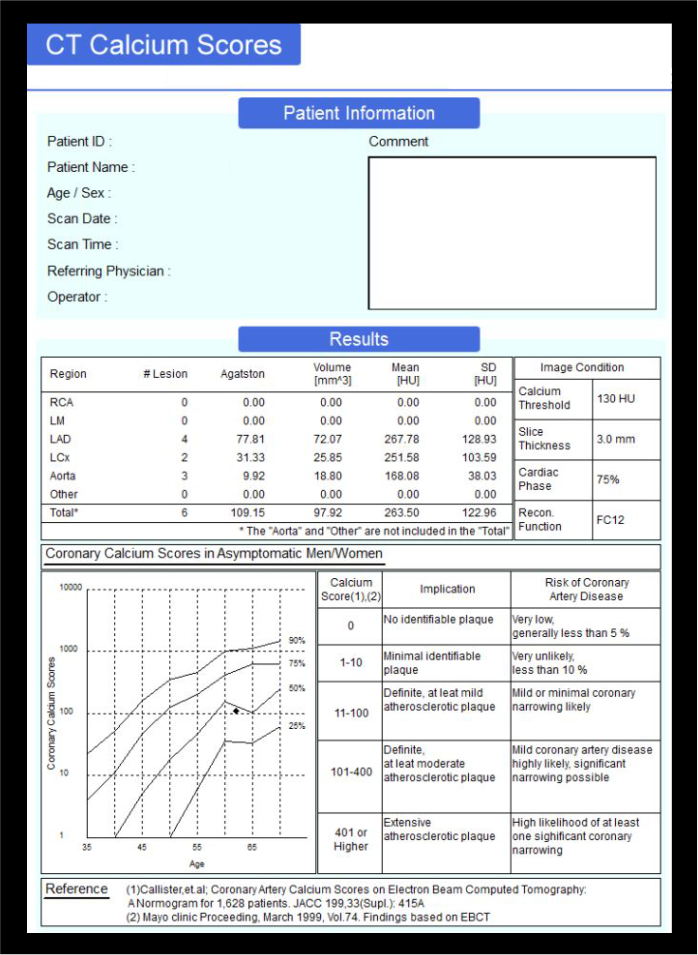

CT calcium score, which is a non-contrast study, is helpful to quantify coronary artery calcium deposits. It’s used for the risk stratification and therapeutic decision making in patients who are in risk of atherosclerotic cardio vascular risk. Moreover, in Transcatheter Aortic Valve Replacement (TAVR), calcium scoring is used to analyze the score of the aortic valve.

- Calcium score analysis report.